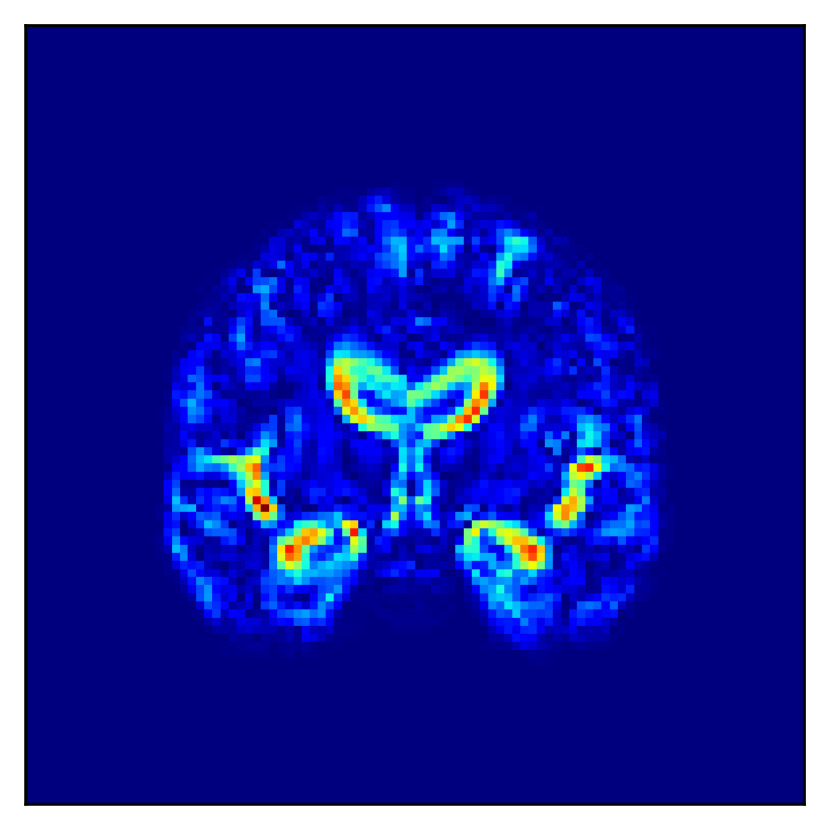

Fig. 5 shows the difference in the reconstructed images (the coronal, sagittal, transverse planes) with and without perturbation to one dimension of the low-dimensional representations that most affect the disease features between AD and CN. This one dimension is chosen to have the largest expected value of the difference in the mean vector ( dim) between AD and CN.

In Fig. 5, the influence of dimensions that may contribute to the diagnosis of AD is examined, and it can be seen that the naïve -VAE captures not only the important areas around the ventricles shown in Fig. 2 but also the edges of the brain and other areas. Loc-VAE, however, is more limited and captures this region better. This result shows that Loc-VAE acquires a specific dimension of the disease features on low-dimensional representation. Disease feature–specific dimensions serve as materials for the neurologist to assess similar cases displayed by CBIR.